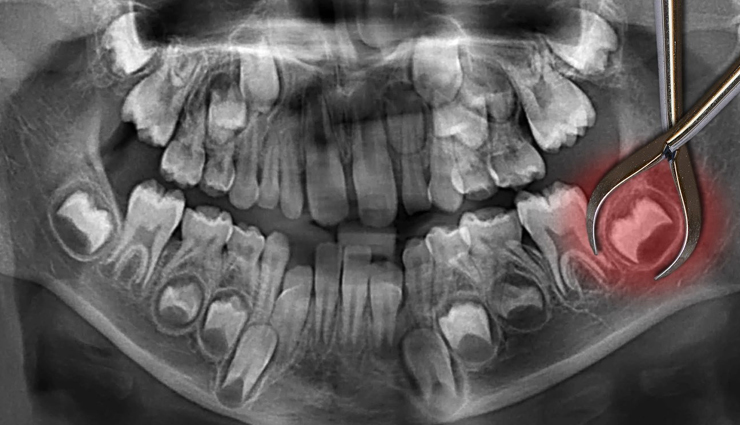

Your decision to remove your wisdom teeth will depend on your circumstances. Your dentist will examine your third molars and take X-rays to determine if your third molars are causing problems or are likely to cause problems in the future. In some cases, they can be left in place if they are not causing any problems or in a position that allows for proper cleaning and maintenance.